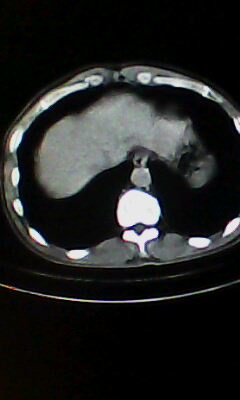

弥漫性肺气肿 但内胆管轻度扩张

口服造影剂是必须的